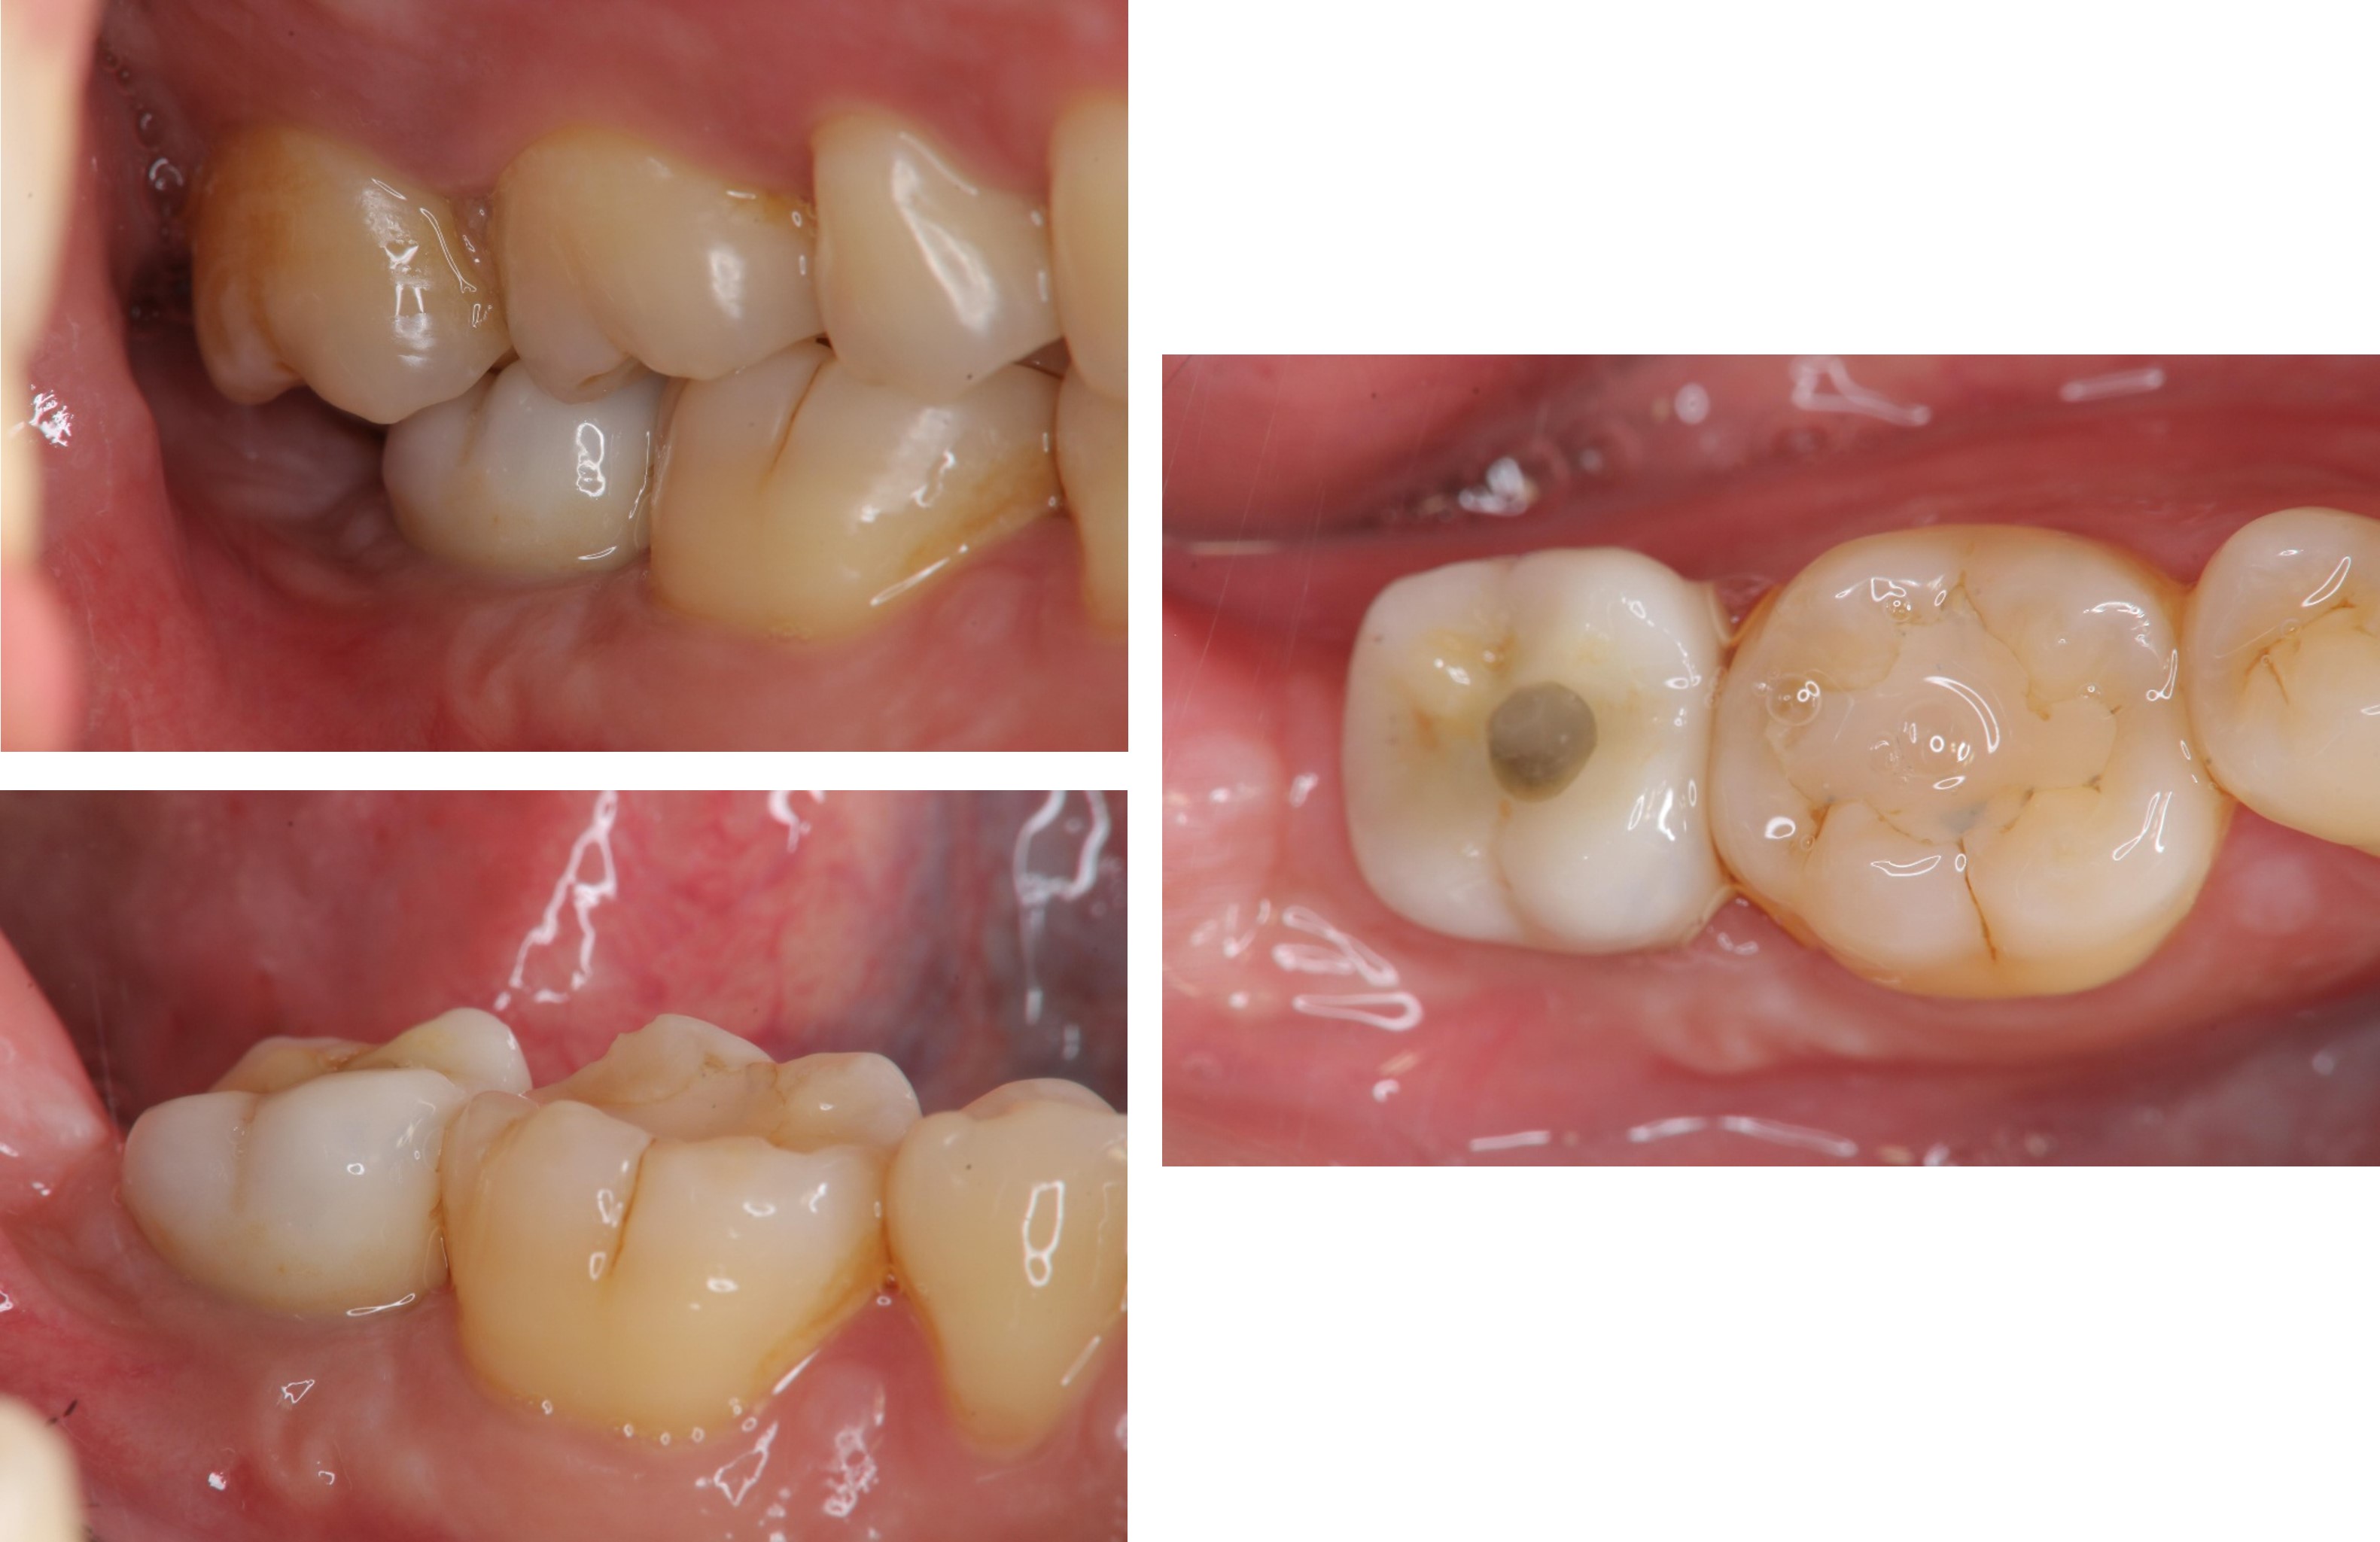

治療前,根管後大臼齒有牙裂

治療前,根管後第一大臼齒有牙裂

植牙前口內評估